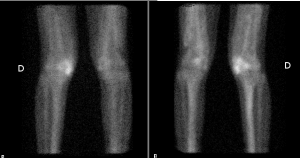

Temps angiographique et tissulaire: accumulation du radio traceur au niveau du genou gauche et dans le compartiment tissulaire antérieur des cuisses

Au temps osseux : hyperfixation peu intense extra osseuse en regard des deux fémurs et hyperfixation intense extra osseuse sur la face interne du genou gauche.

Ossification hétérotopique active de la loge antérieure des deux cuisses en rapport avec une myosite ossifiante immature

Ossification hétérotopique active de la face interne du genou gauche en rapport avec une para ostéo arthropathie neurogène (PAON) immature